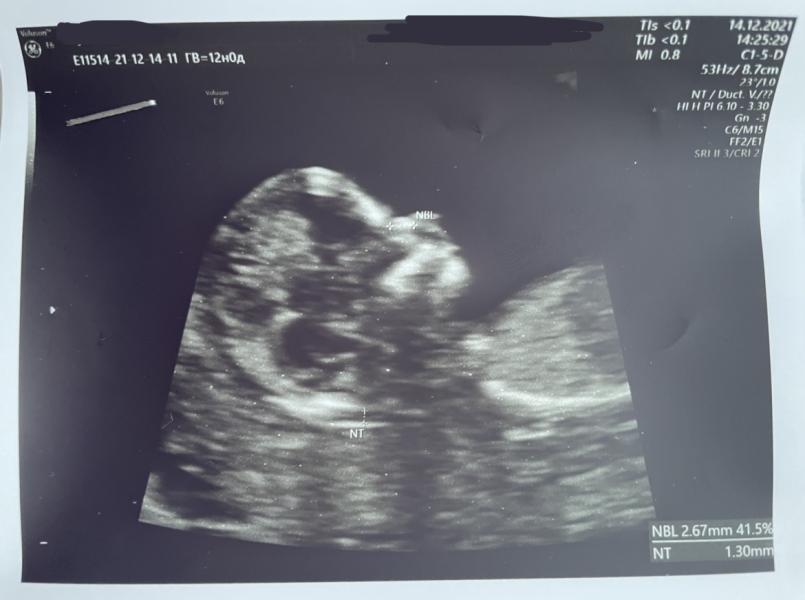

Сегодня 14.12 , 12 недель, сделали первый скрининг ☺️

По узи все хорошо 🙌

Увидела на экране малыша, так дёргался там 😍❤️ Пол конечно же не сказали, да и нам пока не надо знать, главное, чтоб здоровенький 😌

Сказали, что на неделю больше срока 😅